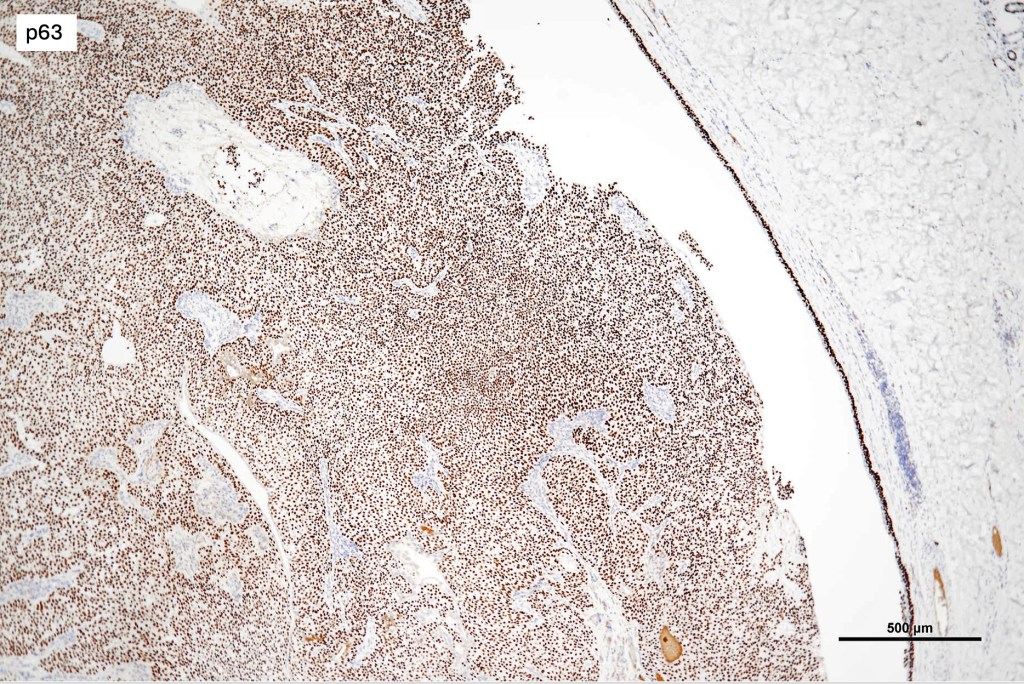

•Squamous differentiation